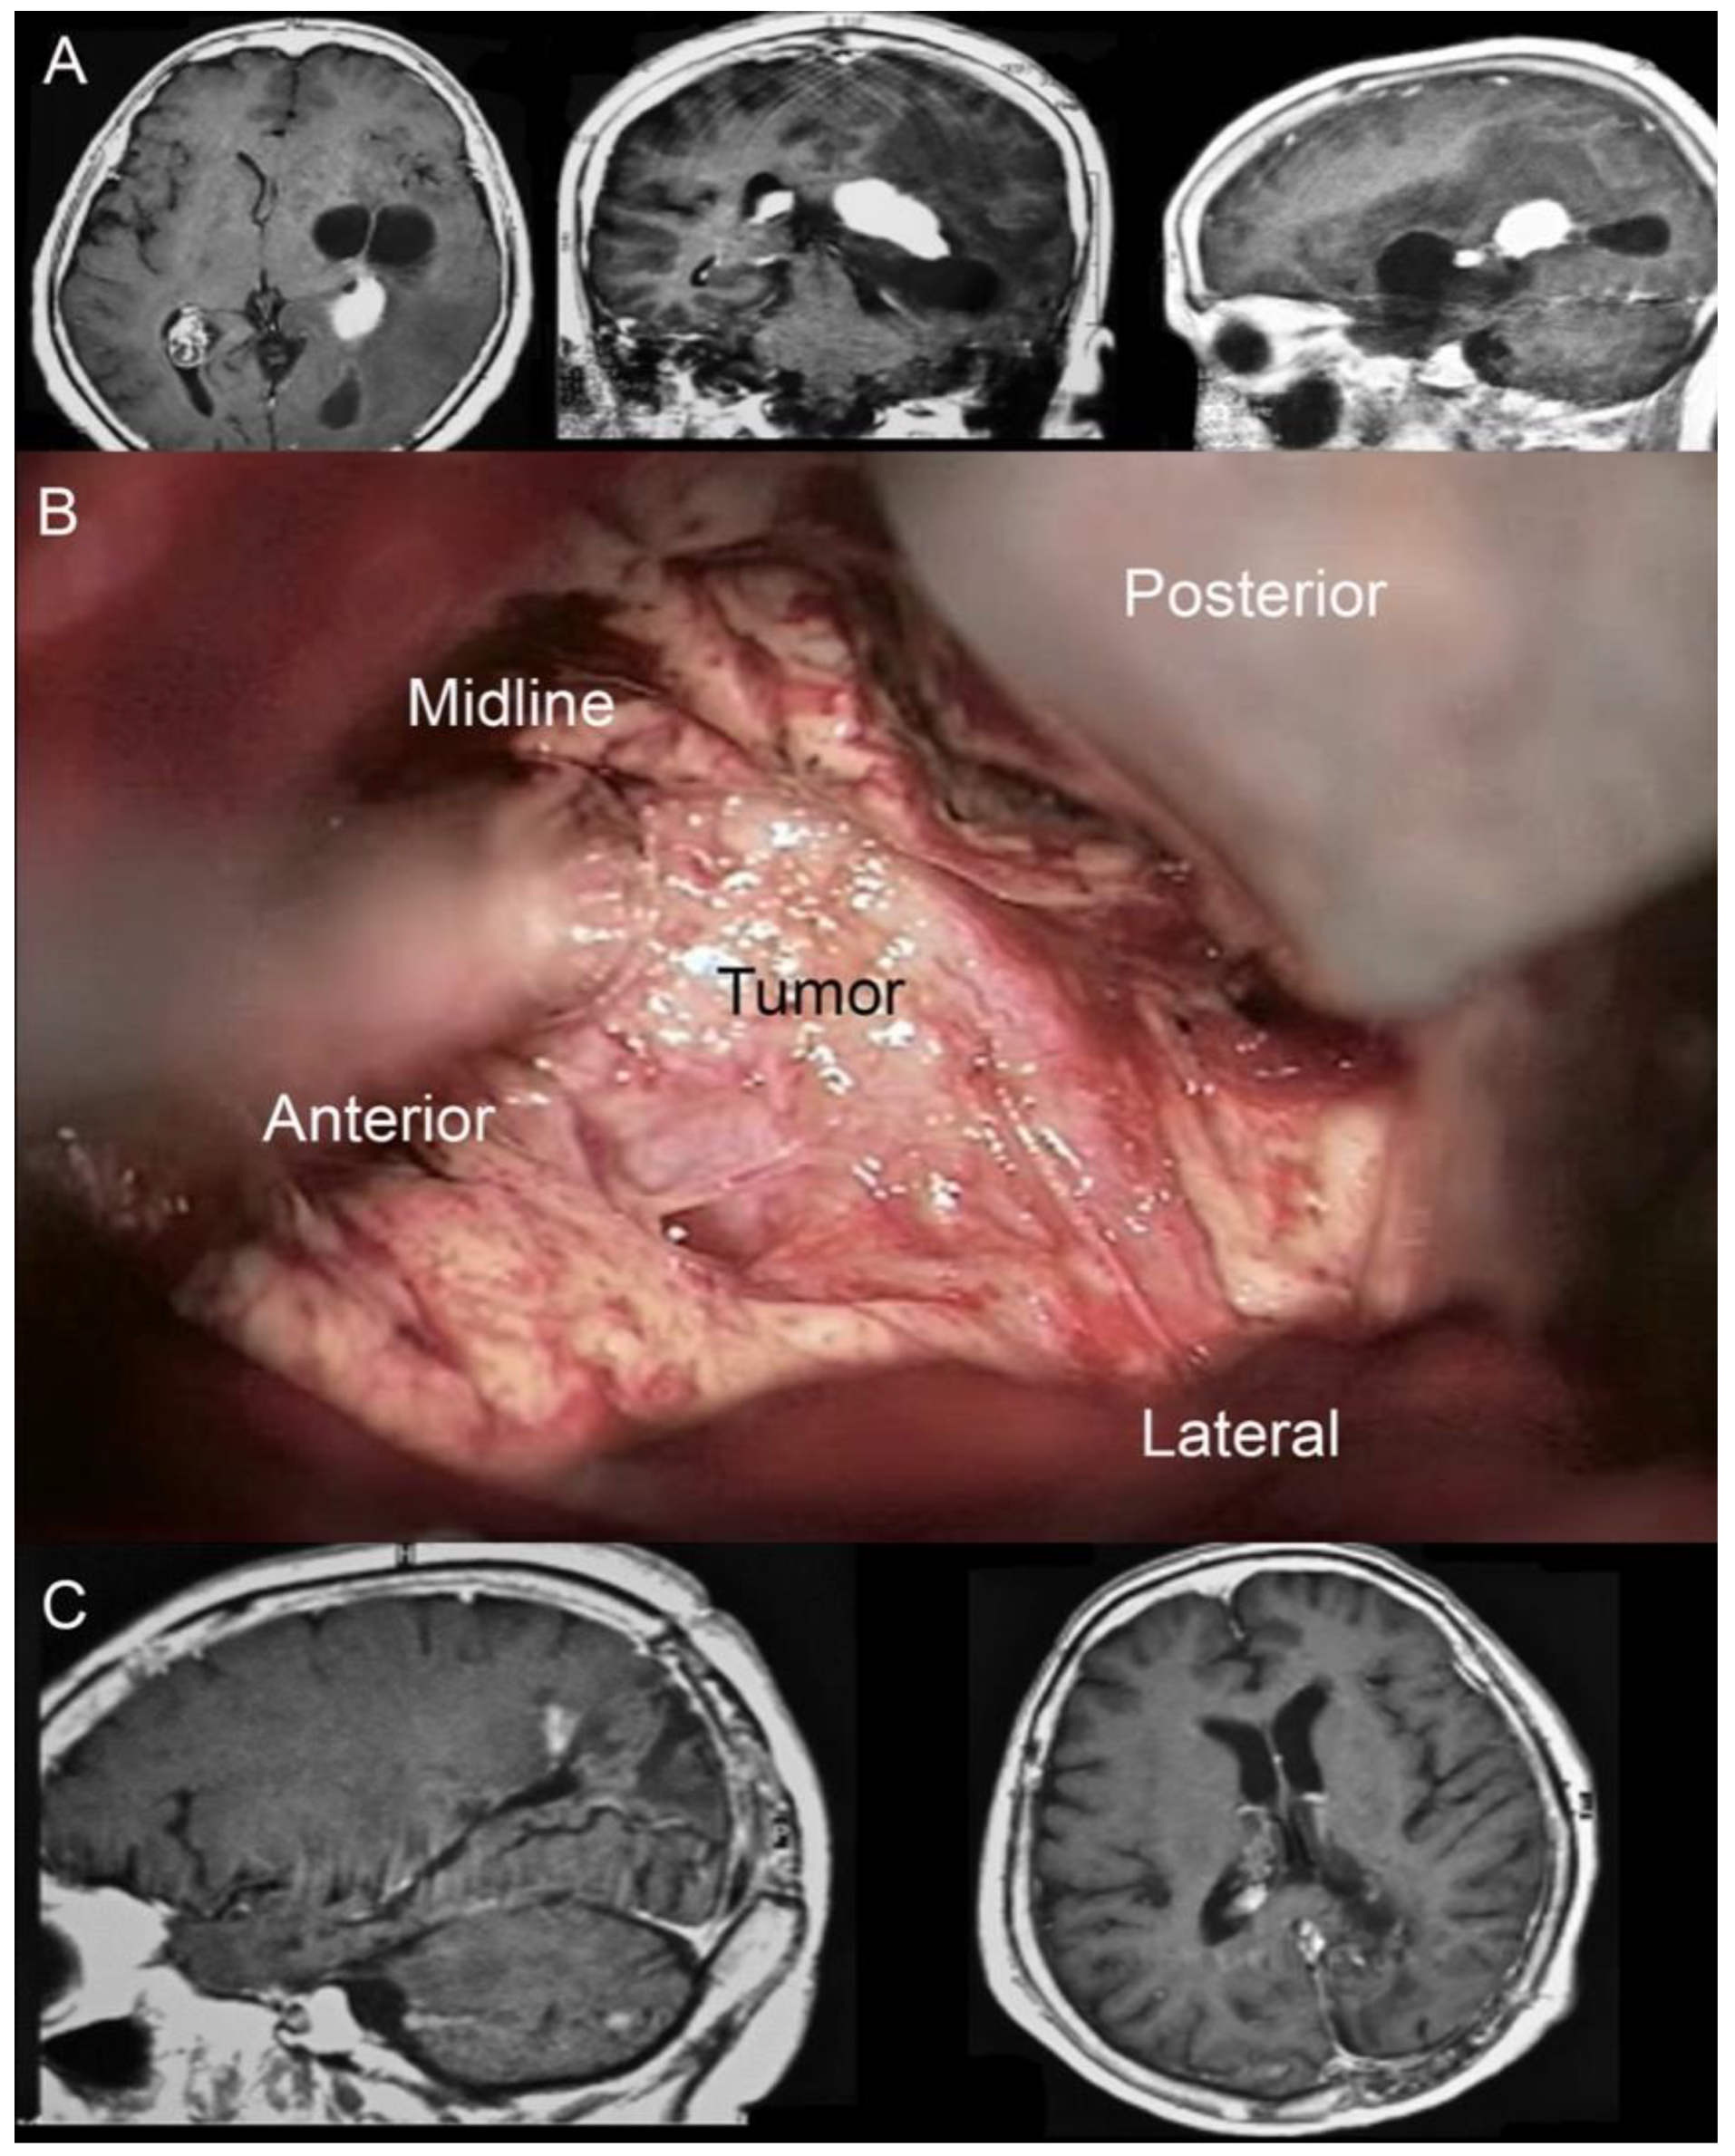

Figure 4. (A) Pre-operative MRI showing a left-sided partially cystic lesion localized in the atrium and partially involving the temporal horn. (B) Intraoperative photograph propaedeutic for videoclip orientation. (C) Postoperative MRI showing complete tumor removal.

• Illustrative case n.1 (Case n.2 in the table, Figure 4)

A 65-year-old female with a clinical history characterized by a slow and progressive reduction of the visual field and chronic headaches came to our attention because of an episode of seizure. A brain MRI showed a left-sided partially cystic lesion localized in the atrium and partially involving the temporal horn. Upon neurological examination, she was observed to have a lateral homonymous hemianopsia. She had normal motor strength in all extremities and no speech disturbances. She was right-handed. The patient underwent surgical removal of the lesion through IITA. Once the interhemispheric window was gained and the parieto-occipital sulcus identified, a 1 cm corticotomy perpendicular to the deepest end of the sulcus and adjacent to the cingulum was performed. Once the atrial cavity was entered, the lesion was identified. Its consistency was very hard. A patient and delicate dissection of the lesion from the surrounding ventricular ependyma was performed by the wise use of suction devices, bipolar forceps, and micro-dissectors. Once the tumor/brain interface was identified all around the lesion’s circumference, the lesion itself was separated into two pieces through the use of the Malis bipolar forceps. The biggest part of the tumor was removed by gently completing the dissection from the surrounding ependyma. Removal of the remnant portion was obtained by repeating the maneuvers used for the biggest portion.

The postoperative course was uneventful. The patient was admitted to the neurocritical care unit, where she was monitored for 24 h. The patient experienced a significant improvement of the visual field disturbances documented by campimetry, and her headache slowly recovered. At a 3-year follow-up, no seizures had been documented. Histological examination showed a choroid plexus papilloma.